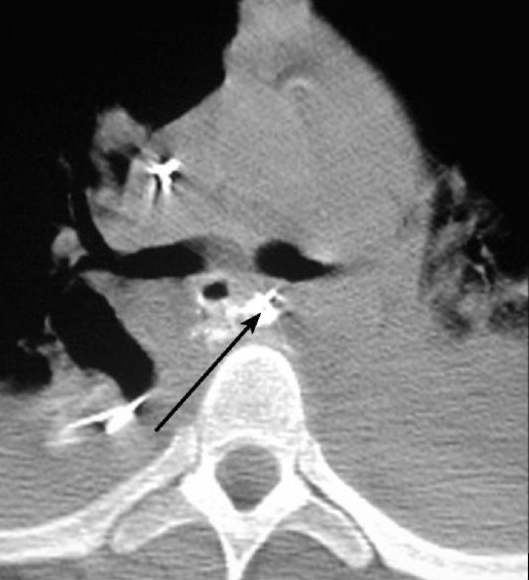

Şəkil 21. KT. Şvannoma. Sol  parakardial sahədə dəqiq kənarlı, homogen törəmə